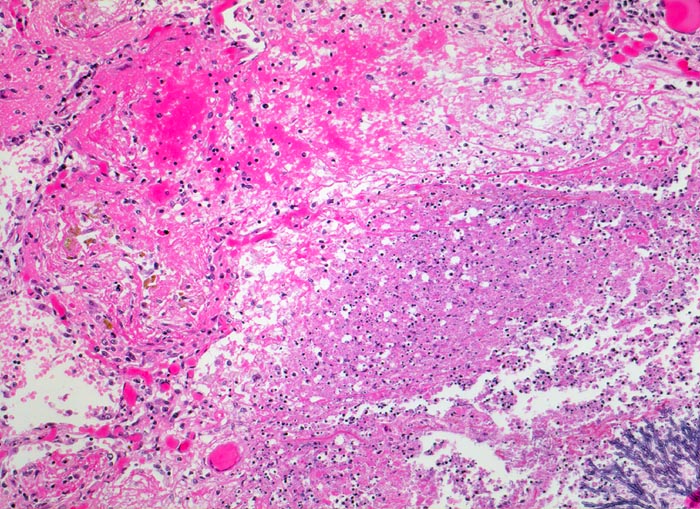

• Multiple Herde mit zentraler Nekrose und hämorrhagischem Randsaum.

• Pilzmyzelien, zerfallende neutrophile Granulozyten und Erythrozyten im Zentrum der Herde.

• Kräftig gefärbte Pilzhyphen mit 45° Verzweigungen.

• Hämorrhagischer Randsaum um die Nekrose: Hyperämische Alveolarwandkapillaren. Alveolen angefüllt mit Blut, Fibrin und Alveolarmakrophagen.